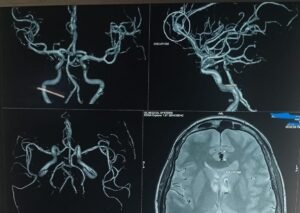

Endovascular Coiling of a Ruptured DACA Aneurysm — A Life-Saving Neuro interventionA 50-year-old woman presented with a sudden thunderclap headache — a hallmark warning sign of subarachnoid hemorrhage (SAH). With a background of irregular hypertension treatment, MRI confirmed:🔍 Diagnosis:Subarachnoid Hemorrhage (Grade 2)Ruptured saccular aneurysm in the left Anterior communicating artery A2 segment🩺 Treatment:An emergency endovascular coiling procedure was performed to occlude the ruptured aneurysm — preserving cerebral circulation while preventing rebleed.✅ Outcome:Modified Rankin Score (mRS): 0 at dischargeNo neurological deficitsEarly discharge within days — full recovery and independenceIR Team Madan Mohan B Kamala Retnam M Anesthetic support Naveen Karthik 💬 Why this matters:Endovascular techniques offer a powerful, minimally invasive treatment options in time-critical situations like aneurysmal SAH.During Brain Awareness Month, let’s amplify the message of:🧠 Early recognition of red-flag neurological symptoms🧠 Rapid imaging and diagnosis🧠 Access to expert endovascular care